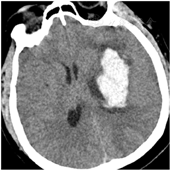

所有患者均在入院后24 h内[4]全麻下行手术治疗。试验组患者术前行头颅CT 1 mm薄扫(图1)、刻盘,并将数据录入神经导航系统;患者全麻取仰卧位,头偏健侧,头架固定并取颅骨标记点进行导航注册,定位手术最佳点,铺单消毒。在患侧颞部切开3~4 cm皮肤切口,充分止血钻孔,切开硬脑膜,通过导航引导组织导管扩张器穿刺至血肿腔内(见封四,图2、图3),取出管芯,将内镜沿组织导管扩张器通道进入血肿腔,由内镜将组织扩张器引导至血肿腔底面,使用吸引器抽吸底面血肿(见封四,图4),直至显露脑组织,向外渐退出组织扩张器,此时见周围血肿回缩至中央,继续抽吸并逐渐退出,依此方式逐渐抽吸血肿至清除完毕,并完全退出扩张器。遇到活动性出血时给予电凝止血,并给予少量明胶海绵覆盖;在创面渗血的地方给予速即沙及少量明胶海绵覆盖。血肿清除完毕后,通过内镜观察残腔无出血及渗血,留置引流管,缝合头皮术毕。